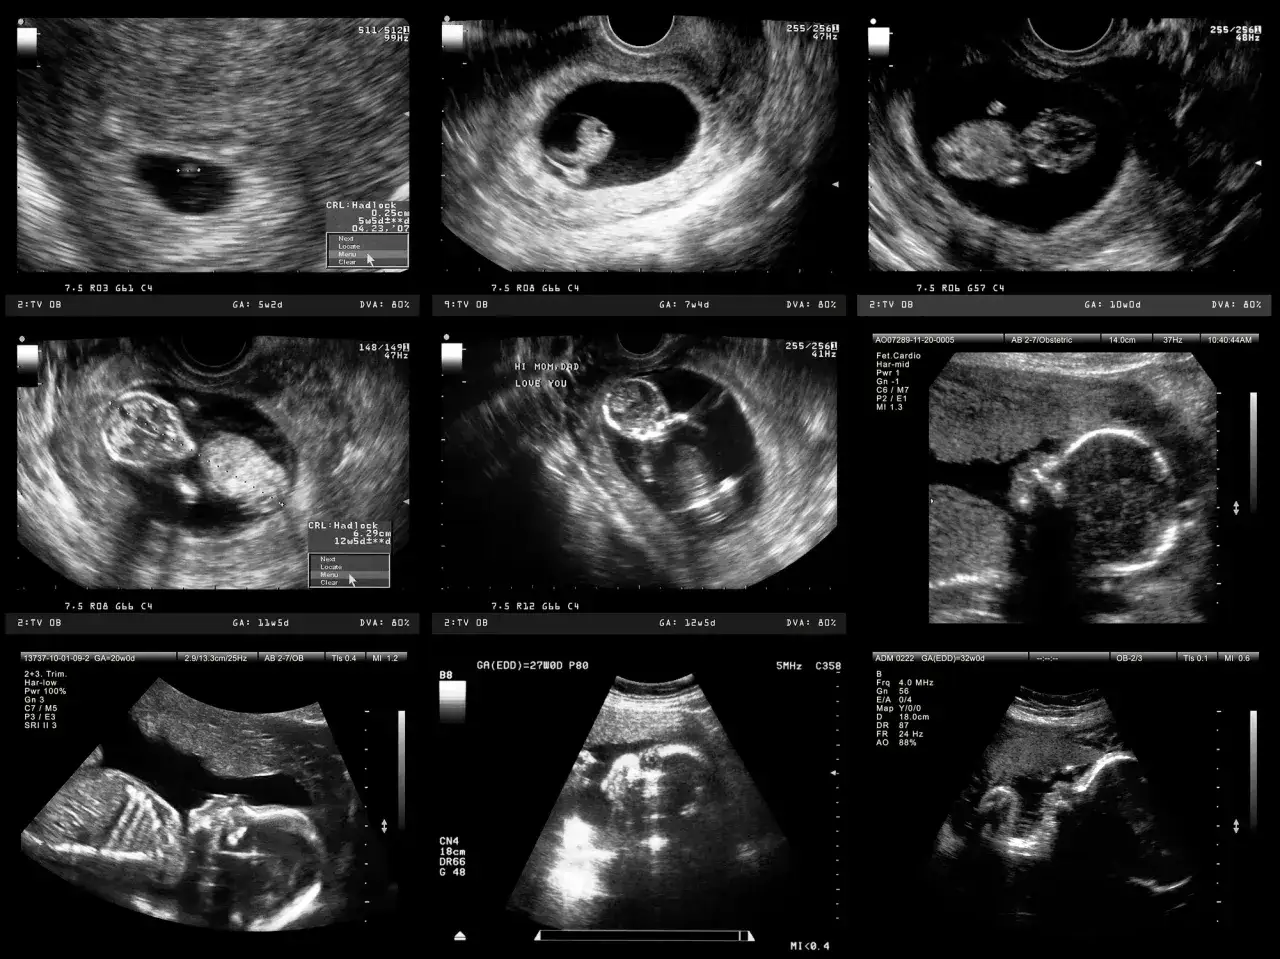

Warto rozróżnić dwa główne typy badań prenatalnych: przesiewowe i diagnostyczne. Badania przesiewowe, takie jak test PAPP-A czy testy NIPT, mają za zadanie ocenić ryzyko wystąpienia pewnych wad genetycznych. Nie dają one jednak ostatecznej diagnozy. Jeśli wyniki badań przesiewowych wskażą na podwyższone ryzyko, lekarz może zalecić badania diagnostyczne, takie jak amniopunkcja czy biopsja kosmówki. Te badania są inwazyjne, ale dają pewną i ostateczną odpowiedź na pytanie o obecność konkretnych nieprawidłowości. Czas oczekiwania na te wyniki jest kluczowy, ponieważ wpływa na dalsze planowanie opieki medycznej i ewentualne decyzje, dlatego tak ważne jest, abyście wiedzieli, czego się spodziewać.

Krok pierwszy: Badania przesiewowe I trymestru jak szybko otrzymasz wynik testu PAPP-A?

Test PAPP-A, często nazywany testem podwójnym, to jedno z pierwszych badań przesiewowych w ciąży. Na sam wynik biochemiczny z krwi czeka się zazwyczaj od 2 do 10 dni roboczych. Pamiętajcie jednak, że ostateczny, zintegrowany wynik, który łączy dane z badania krwi z wynikami USG I trymestru, otrzymacie i omówicie dopiero podczas wizyty u lekarza prowadzącego. To właśnie on, analizując wszystkie parametry, przedstawi Wam pełny obraz ryzyka.

Nowoczesna precyzja: Czas oczekiwania na nieinwazyjne testy NIPT (Sanco, Harmony, Nifty)

Nieinwazyjne testy prenatalne (NIPT) to coraz popularniejsza metoda oceny ryzyka wad genetycznych. Czas oczekiwania na ich wyniki może się różnić w zależności od wybranego testu i miejsca, w którym próbka jest analizowana:

Amniopunkcja: Jak długo czeka się na szybki wynik FISH, a ile na pełny kariotyp?

Amniopunkcja to inwazyjne badanie, które pozwala na pobranie płynu owodniowego do analizy. W jej przypadku możecie spodziewać się dwóch rodzajów wyników:

Biopsja kosmówki: Kiedy poznasz ostateczną diagnozę po tym badaniu?

Biopsja kosmówki to kolejne inwazyjne badanie, które, podobnie jak amniopunkcja, dostarcza materiału genetycznego do analizy. Czas oczekiwania na wyniki jest zbliżony do amniopunkcji. Wstępny wynik można uzyskać w ciągu kilku dni (nawet 48 godzin), natomiast na pełny wynik z hodowli komórkowej czeka się od około 10 dni do nawet 3 tygodni. W obu przypadkach, zarówno przy amniopunkcji, jak i biopsji kosmówki, to oczekiwanie jest najtrudniejsze, ale pamiętajcie, że jest ono kluczowe dla uzyskania pewnej diagnozy.